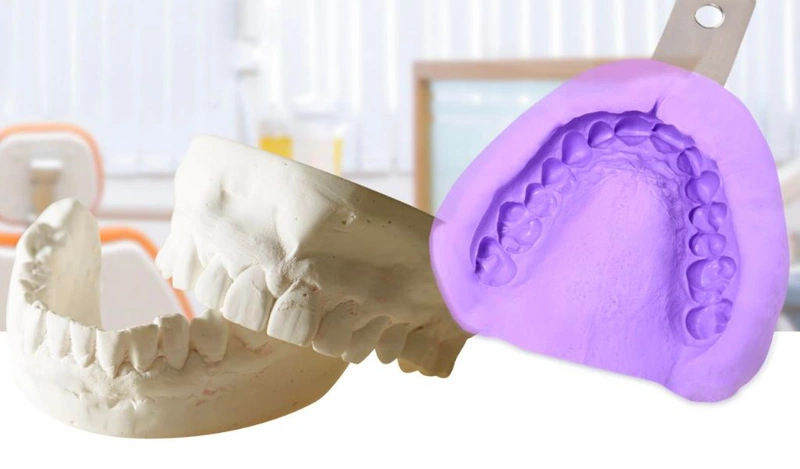

Lấy dấu răng cho niềng là bước thăm khám đầu tiên và quan trọng, nhằm thu thập dữ liệu giải phẫu chính xác về răng, xương hàm

Lấy dấu hàm tháo lắp là một kỹ thuật phục hình đặc biệt, có ý nghĩa quyết định đến sự thành công của hàm giả tháo lắp.

Lấy dấu răng là quá trình tạo bản sao âm bản của răng và mô mềm trong miệng. Khuôn mẫu này sau đó được đổ thạch cao